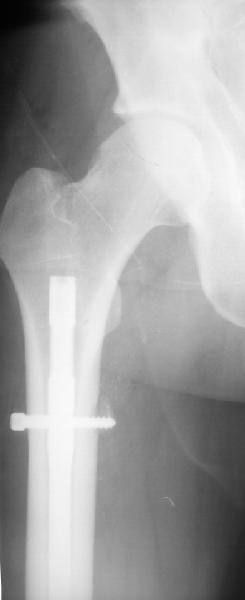

Уважаемые коллеги,пожалуйста, подумайте над следующим ребусом. В нашу клинику поступилпациент из области, 17лет, получивший травму в ДТП 25.08.04, открытый перелом бедра, при поступлении наложено скелетное вытяжение.

30.09.04 на операции выявлен вывих бедра и перелом голени на этой же стороне. Остесинтез бедра все же выполнен, и по заживлении раны пациент переведен к нам. Кроме того у пациента нейропатия седалищного нерва на этой же стороне. В нашей клинике планируется наложение аппарата таз-бедро, для постепенного низведения бедра с последующим открытым вправлением, замена фиксатора на запираемый гвоздь и блокируемый остесинтез голени. Вариант с первичным эндопротезированием мы не рассматривали из-за юного возраста пациента. Вопрос с чего начать? Кроме того, сгибание в коленном суставе в настоящее время (95 градусов) затрудняет остеосинтез голени.Стоит-ли менять гвоздь? Или же спилить торчащий конец во время открытого вправления? Может, попробовать все сделать одномоментно? Заранее спасибо.

На мой взгляд, на ренгенограмме таза (левый сустав) имеется (имелось) перелом заднего края вертлужной впадины, перелом ацетабулум-вывих головки? (нужны дополнительные снимки).

Очень трудно угадать, когда вывих произошел: во время травмы или во время операции на бедре, хотя около 5% переломов бедра сопровождаются переломами шейки бедра, 15-60% с минимальными смещениями и до 30% первично не распознаются.